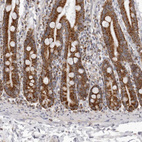

Immunohistochemical staining of human duodenum, endometrium, kidney and testis using Anti-TUFM antibody HPA024087 (A) shows similar protein distribution across tissues to independent antibody HPA018991 (B).